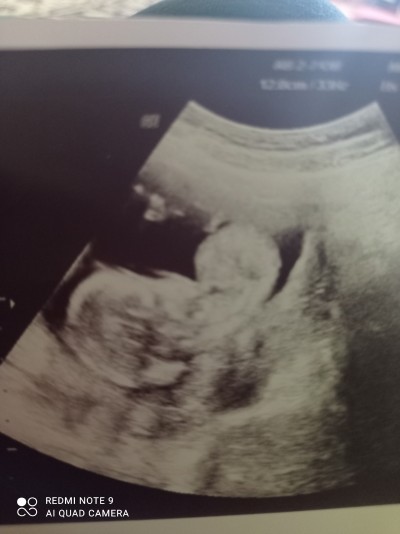

Bebek ultrasonuna bakıp cinsiyet tahmini yapabilen anneler varmış bana da yapabilir misiniz

Gebelik haftası 16+1

Yanı bunun için çok erken dha geblik haftan nedir ama kıza benzyo sanki

Evet yanlış anladım. Kıza benzyor Sanki duruşu falan

16 haftalıksan doktorununda bir tahminde bulunması gerekir canım, ** aynen kıza benzettim duruş pozisyonundan yinede bilemedim

Detaylı ultrasonda net belli olur canım ama ilk kiziminda şimdiki bebegiminde aynı haftalarda ultrason fotoğrafı var erkeklerin kafa yapısı ve duruşu daha farklı oluyor ben bakınca anladım şahsen farki sizinkide benim kızımın ultrasinuna benziyor

Biri cok kucuk anlasilmiyor. Ama diger resimde kiz gibi

:)İçimden kız geçti nedense

Erkek gibi geçti içimden

Benimde o haftalar  kesem o sekildeydi  bence kız  :)

Kıza benziyor canım